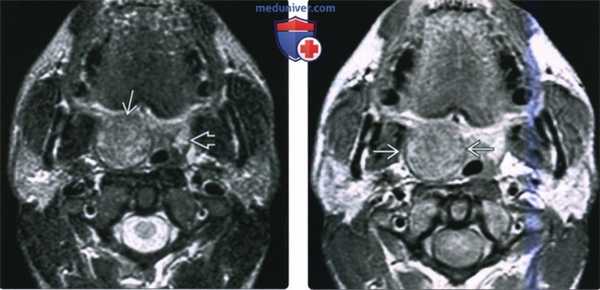

(Слева) МРТ Т2ВИ FS МРТ, аксиальная проекция, на которой визуализируется неходжкинская лимфома правой небной миндалины, контуры образования четкие. Поскольку с возрастом объем лимфоидной ткани снижается, небольшой размер левой небной миндалины является нормой. Плоскоклеточный рак или доброкачественная смешанная опухоль могут выглядеть идентично, и только биопсия позволит установить диагноз лимфомы.

(Справа) МРТ Т1ВИ с КУ, аксиальная проекция, тот же пациент. Лимфома однородно накапливает контрастное вещество. При воспалении миндалины контраст бы накапливался отдельными полосами, в случае интра-тонзиллярного абсцесса в центре образования обнаруживается очаг некроза.

(Слева) MPT Т2ВИ FS в аксиальной проекции. В обеих небных миндалинах определяются мультифокальные лимфомы. Четкие края опухолей говорят о том, что они находятся в пределах капсул миндалин.

(Справа) MPT Т1ВИ FS с КУ, аксиальная проекция, этот же пациент. Определяется участок лимфомы в области лимфоидной ткани корня языка слева и крупный некротизированный лимфоузел IB уровня. На шее также визуализируются несколько мелких лимфоузлов, но установить, поражены ли они лимфомой, можно только при помощи метаболических исследований, например, ПЭТ/КТ.

(Слева) На аксиальной МРТ (Т2 ВИ FS) определяется хорошо отграниченная НХЛ миндалины справа. Небольшой размер левой миндалины является нормой для взрослых людей, т. к. лимфоидная ткань подвергается возрастной инволюции. Плоскоклеточный рак миндалины и доброкачественная смешанная опухоль могут выглядеть идентично, диагноз НХЛ подтверждается только при помощи биопсии.

(Справа) На аксиальной МРТ (Т1 ВИ С+) у этого же пациента определяется однородное контрастирование НХЛ миндалины. При инфекционном поражении миндалин наблюдается «исчерченная» картина контрастного усиления, абсцесс миндалины характеризуется центральным некрозом.

(Слева) На аксиальной МРТ (Т2 ВИ FS) определяется мультифокальная НХЛ обеих небных миндалин. Четкие края позволяют предположить, что опухоль ограничена капсулой миндалин.

(Справа) На аксиальной МРТ (Т1 ВИ FS) у этого же пациента визуализируется дополнительный участок поражения лимфоидной ткани НХЛ в основании языка слева, а также крупный некротический лимфоузел IB уровня. Присутствуют множественные мелкие шейные лимфоузлы, однако лишь оценка метаболической активности с помощью, например, ПЭТ/КТ, позволяет выявить их поражение НХЛ.